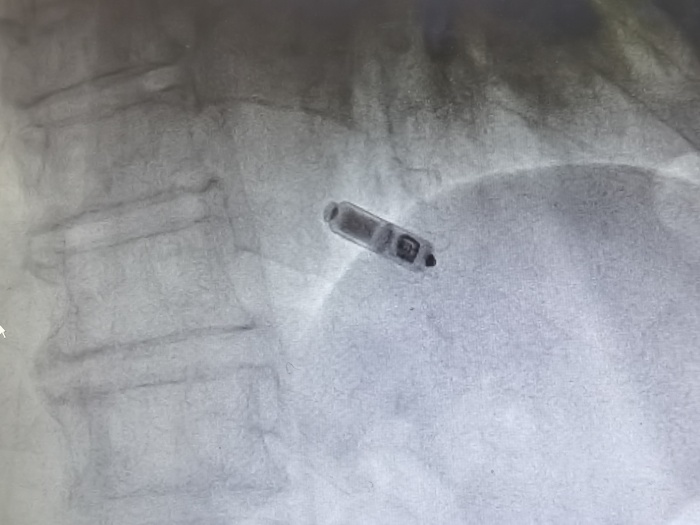

(圖示為植入心臟內(nèi)的Micra? AV無導(dǎo)線起搏器)

金奇志主任醫(yī)師告知:“無導(dǎo)線起搏器是集脈沖發(fā)生器與電極導(dǎo)線于一體的新型起搏器,無需靜脈植入心內(nèi)膜導(dǎo)線,通過以“微縮膠囊”的形式植入患者的心腔內(nèi)。無導(dǎo)線起搏器植入簡單、美觀,無囊袋及導(dǎo)線植入相關(guān)并發(fā)癥,不影響肢體活動,可以明顯提高患者的自信心和治療體驗,安全性與穩(wěn)定性也比較好?!?